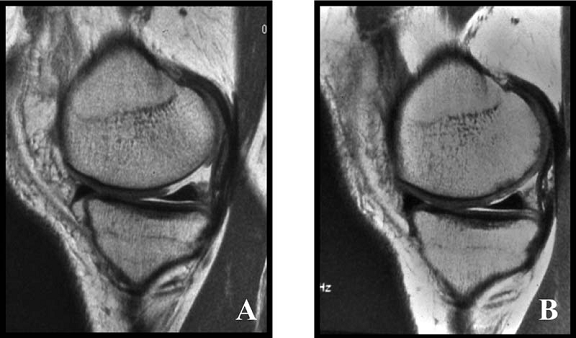

Fig.34. A-scanare inaintea microfracturarii, B-scanare la patru luni dupaa microfracturare.

Evaluarea imaginilor RMN a fost realizata de catre radiologist cu experienta, care cunostea situatia pacientilor si operatia efectuata. Imaginile au fost astfel analizate incat sa se observe zonele cu cartilaj de reparare comparativ cu cel nativ. Repararea morfologica a fost descrisa ca depresiva, neteda, sau mareata comparativ cu cartilajul nativ inconjurator. Volumul de umplere al defectului cu cartilaj reparator a fost masurat folosind imagini sagitale si coronale si a fost gradat ca bun (intre 67% si 100%), moderat (34% la 66%), sau slab (0% la 33%) pe baza procentajului defectului umplut. Interfata cu suprafata cartilajului nativ adiacent a fost evaluata si gradata ca fiind mica ( gaura ≤ 2mm) sau mare (gaura ˃ 2mm). Edemul maduvei osului subcondral a fost gradat ca fiind usor (˂ 1 cm²), moderat (intre 1 si 3 cm²) sau sever (˃ 3 cm²), iar prezenta sau absenta cresterii osoase a fost atent inregistrata.

Imaginile rezonantei magnetice au demonstrat un semnal hiperintens al cartilajului reparator la 22 de pacienti (92%) din cei 24 si usoare edeme subcondrale la 17 pacienti (71%). Umplerea cu cartilajul reparator a fost clasificata ca fiind buna ( 67% la 100%) la majoritatea pacientilor, dar cele mai multe leziuni tratate demonstreaza deprecierea morfologiei cartilajului reparator in cartilaj hialin adiacent. Pentru 6 pacienti au fost disponibile RMN-uri secventiale si toate au demonstrat cel putin un grad de umplere moderat. Nu au existat deteriorari al volumului de umplere la acesti pacienti, dar un pacient a avut o crestere a volumului de umplere in timp. Nu s-a gasit o corelare statistica intre volumul cartilajului reparator si timpul scurs de la microfracturi (r=0,173; p=0,420). Cresterea osoasa a fost demonstrata la sase pacienti (25%). Doua treimi din acestia au avut un grad bun de umplere. Toti cei 13 pacienti cu un bun grad de umplere au avut o imbunatatire a scorului activitatilor zilnice, pe cand doar 3 pacienti cu umplere moderata a defectului si doar unul cu slaba umplere au avut o crestere a acestui scor (p < 0,05). Similar, scorul componentei fizice SF-36 si rata subiectiva a crescut semnificativ la pacientii cu un grad bun de umplere observat in imaginile rezonantei magnetice (p < 0,05). Descresterea scorului functional dupa 24 de luni a fost observata la toti pacientii cu un slab grad de umplere dupa microfracturi, pentru 2 pacienti cu un grad moderat de umplere (p= 0,097) si pentru 3 pacienti cu grad bun de umplere (p < 0,05). Scorul activitatilor zilnice (p < 0,05; r = 0,385) si scorul componentei fizice SF-36 (p ˂ 0,05; r = 0,388) obtinute in timpul rezonantei magnetice demonstreaza o corelatie statistica pozitiva cu gradul de umplere.